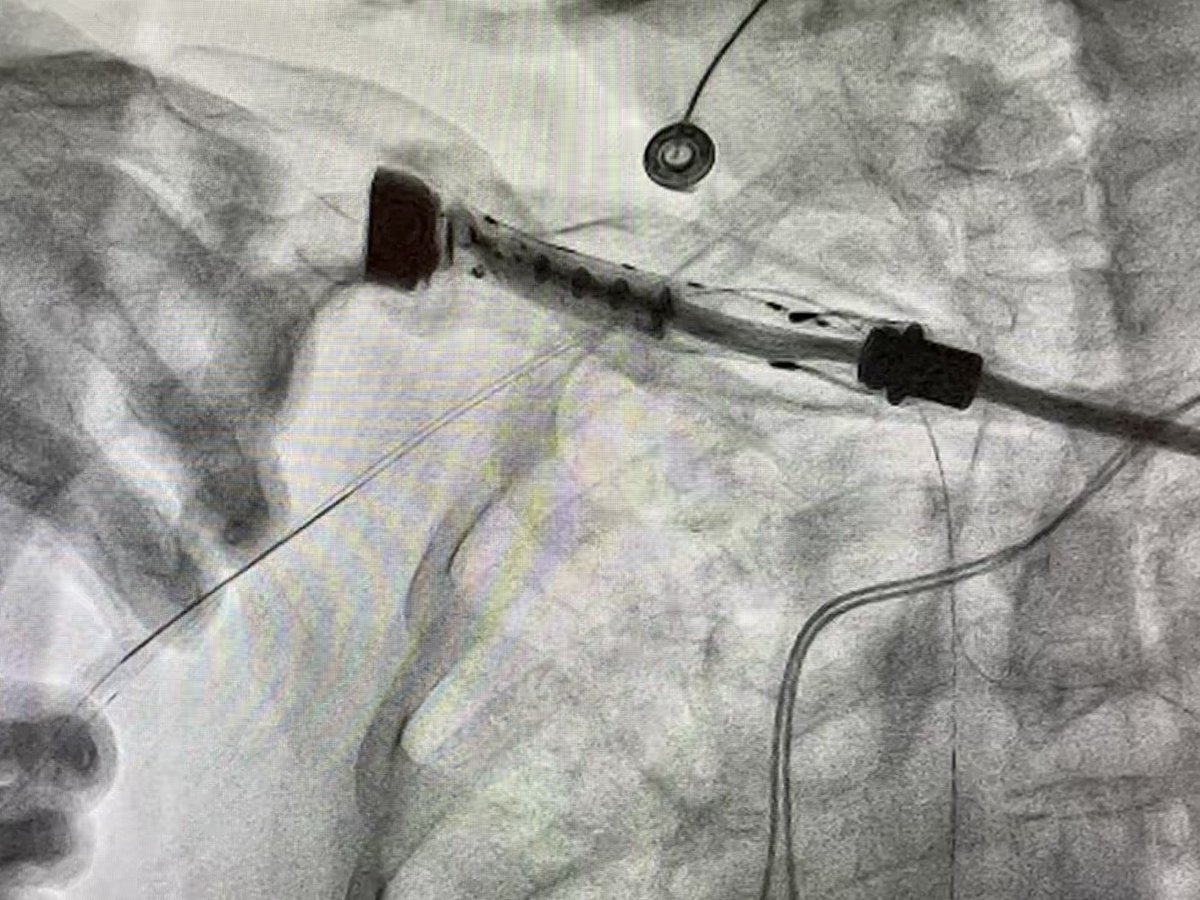

#PercAx #TAVR. Single Perclose. Dry closure. Post angio showed mild extravasation. Ten minutes manual pressure and repeat angio was pristine. No Perclose Pinch. No need for covered stent.

willsuh76's tweet image. #PercAx #TAVR. Single Perclose. Dry closure. Post angio showed mild extravasation.  Ten minutes manual pressure and repeat angio was pristine. No Perclose Pinch. No need for covered stent.